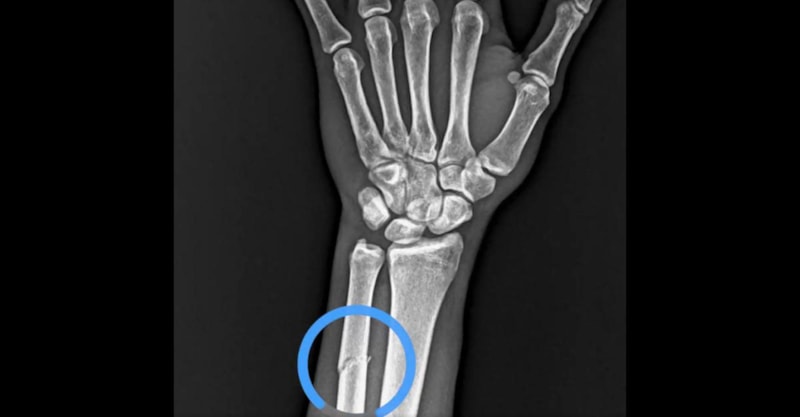

Bordo-mavililer, "VAR’da göremediğiniz pozisyonun röntgen görüntüsü. Adaletiniz batsın." başlıklı bir video paylaştı ve görüntülerde Onuachu'nun röntgen görüntüsüne yer verdi.

Kırık tespit edildi

Öte yandan Trabzonspor'dan yapılan açıklamaya göre, oyuncunun kolunda kırık tespit edildiği öğrenildi.

Beşir, "Futbol A Takımımızın Başakşehir ile oynadığı karşılaşma esnasında sakatlanarak oyundan çıkan futbolcumuz Paul Onuachu’nun yapılan muayenesinde sol kasık bölgesinde kas (adduktor kas grubu) yaralanması ve sol önkolda darbeye bağlı ayrışmamış kemik (ulna) kırığı tespit edilmiştir. Oyuncumuzun tedavisine sağlık ekibimizce başlanılmıştır" dedi.